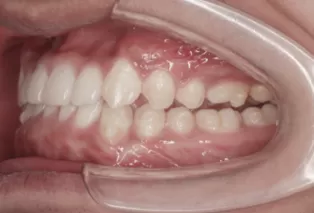

Intraoral photos